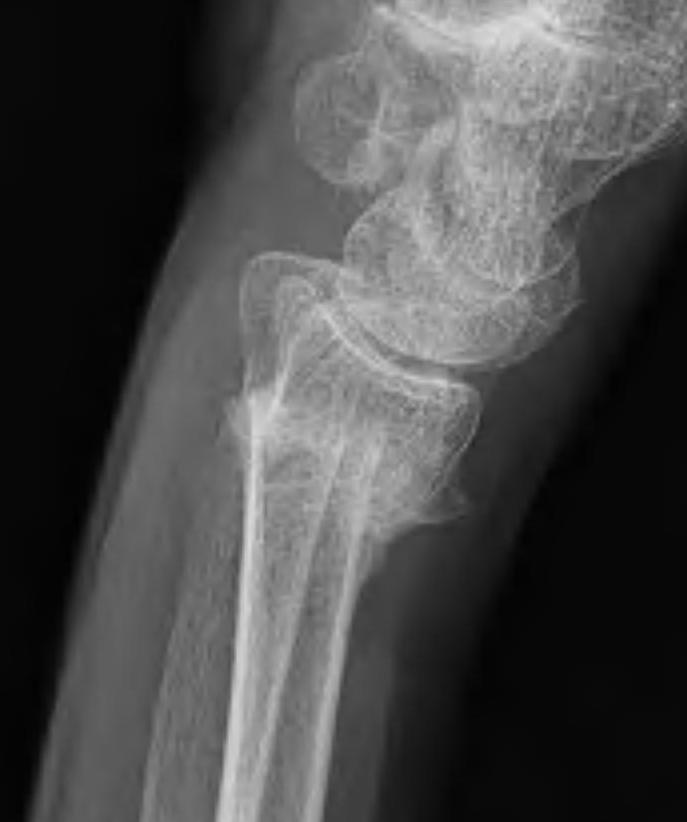

Xray

Bilateral xrays

PA film in neutral

- wrist neutral

- elbow & shoulder at 90°

Malunion

| Radial shortening | Radial inclination | Positive ulna variance |

| Dorsal tilt > 15 degrees | Volar tilt > 10 degrees | Articular step > 3 mm |

Dorsal tilt

- loss of flexion

- +/- midcarpal instability - DISI / CIND without interosseous ligament disruption